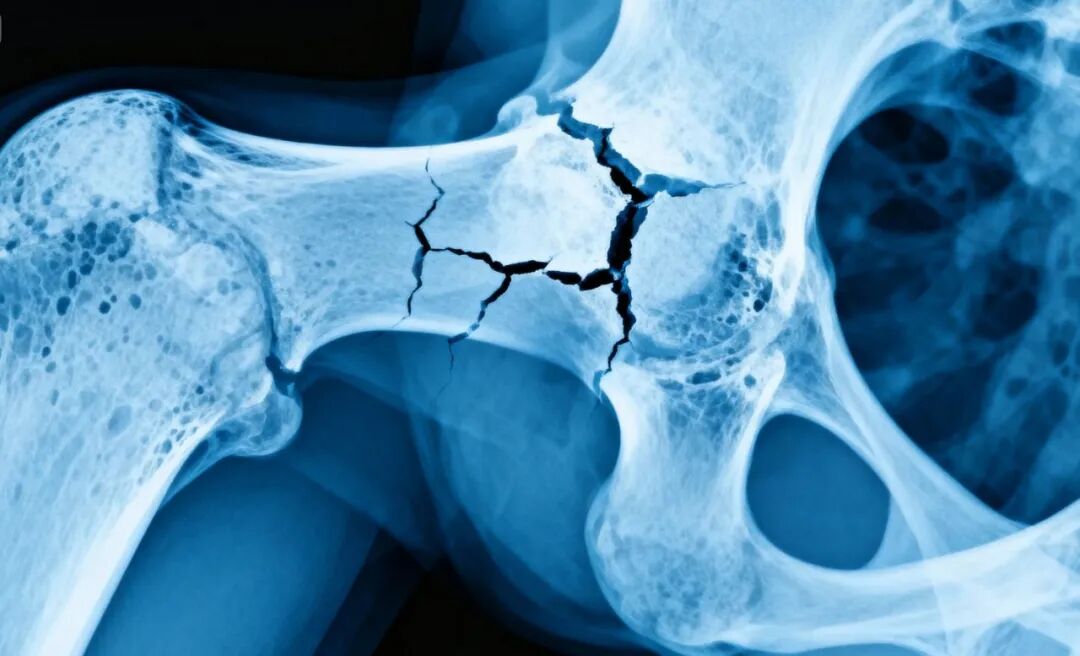

病理性骨折,是指骨骼本身已经因为某种疾病变得脆弱,即使在正常活动或轻微外力下,也容易发生的骨折。可以把它想象成一堵内部被蛀空的堤坝,表面看起来完好,实则不堪一击。

骨质疏松:最常见的原因,尤其多见于老年人。骨骼密度下降,变得像“饼干”一样酥脆。 骨肿瘤:无论是原发于骨骼的肿瘤,还是从其他器官转移来的肿瘤,都可能破坏骨骼结构。 骨感染:如化脓性骨髓炎,会破坏骨组织。 内分泌疾病:如甲状旁腺功能亢进,会导致钙质从骨骼中流失。 遗传性骨病:如成骨不全(“瓷娃娃”病),骨骼天生脆弱。